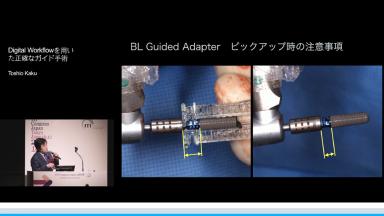

インプラント治療の長期的安定のためには、的確な診断とシミュレーション通りの正確な埋入が必須である。治療計画で重要なのはサーフェススキャンデータとCTのDICOMデータの正確なマッチングである。この講演ではアーチファクトや無歯顎・多数歯欠損症例でマッチングが困難となル場合の対応策について言及している。また、遊離端でガイドの沈下防止法など日常臨床の取り組みについても解説している。

歯肉形態を考慮した正確な埋入ポジションの決定法法について知る

ストローマンガイドの臨床的な修正方法について知る